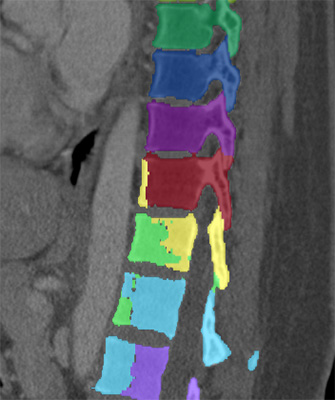

We trained and evaluated the method with five sets of CT and MR scans that visualize the spine. Reference segmentation masks for four of these datasets are publicly available, which allowed for a comparison with other publications that used the same data. Examples of images from the datasets are shown in Figure 3.

Similar performance was achieved for vertebra segmentation in various CT datasets with an average Dice score of and for vertebral body segmentation in an MR dataset with an average Dice score of . Surface distances were lower on CT images compared to MR images ( vs. ), however, there were also fewer training scans available in the MR dataset. Figure 4 illustrates the magnitude of differences of the automatic segmentations from the ground truth segmentations.

(a) Low-dose chest CT

(b) Lumbar spine CT (xVertSeg.v1 dataset)

(c) Lumbar spine MR